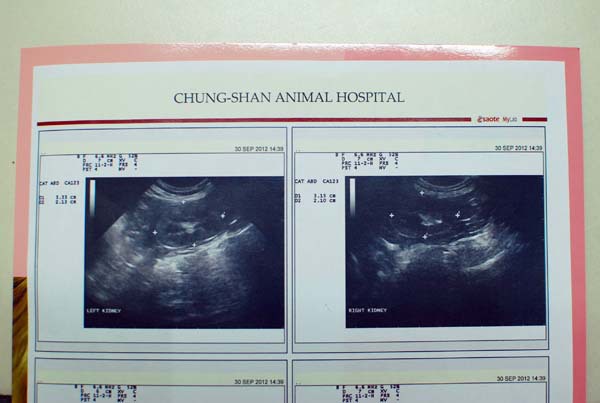

第1.2張是腎臟,有結石

左邊結石:3.33/2.12(3月數值2.03)

右邊結石:3.15/2.10(3月數值1.96)